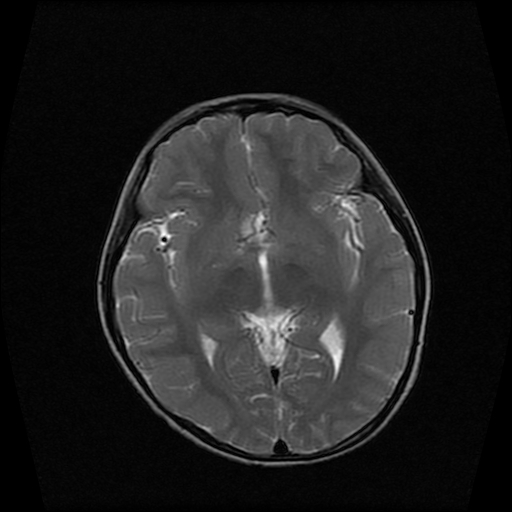

男性,12岁。反复头痛呕吐半月。脑积液无异常。病变部位ct值32hu,dwi无异常。

鞍上为主,累及鞍内,垂体受压位于鞍底。mri呈短t1、长t2信号,不太支持生殖细胞肿瘤,首考颅咽管瘤。

鞍内囊性占位性病变,t1wi、t2wi,均为高信号影。ct平扫为等密度。发病年龄较小。故首先考虑颅咽管瘤,可以做ct增强扫描

鞍内囊性占位性病变,t1wi、t2wi,均为高信号影。ct平扫为等密度。发病年龄较小。故首先考虑颅咽管瘤。